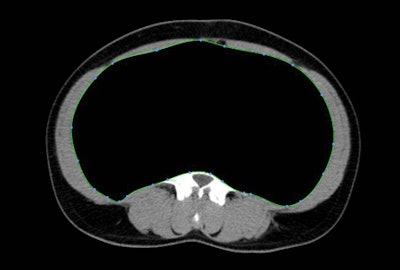

| Fatty regions were isolated and measured based on attenuation of CT images at a single slice (L4/5 intervertebral disk + 6 cm). All images courtesy of Áine Ní Laoire and lead investigator Dr. Michael Maher, University of Cork, Ireland. |

![]() |

All fat measurements were taken at a single CT slice location (L4/5 intervertebral disk + 6 cm), with investigators measuring visceral adipose tissue area (VAT area, cm2) and subcutaneous adipose tissue area (SAT area, cm2) based on tissue attenuation ranging from -150 to -50 HU. Body mass index was calculated from measurements taken at the L1 level, and CT images were examined using an open-source software package (OsiriX, Geneva), Laoire said. Fifty images were randomly selected for reliability testing using the Bland-Altman method and were found to be acceptable.